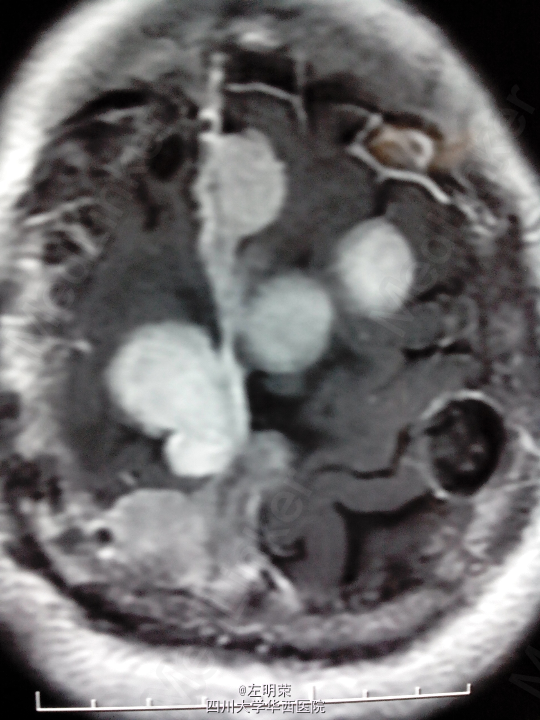

脑膜瘤术后复发(多发脑膜瘤)

左下肢乏力伴间断抽搐半年+, 患者于5年前行左侧额叶脑膜瘤切除术,术后行伽马刀治疗数次,近来出现肢体无力伴抽搐,不规律服用抗癫痫药物,昨日再发抽搐。

1、多发脑膜瘤 2、继发性癫痫

行占位切除术;待病理结果;术后应复查头部MRI,确定肿瘤切除情况,拟定下一步治疗方案。